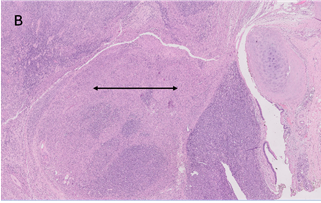

The microscopic examination

revealed a tumour composed of oval to spindle cells arranged in sheets with

interspersed thin-walled blood vessels and separated by focal hyalinized stroma

(Figure 3A). A few areas resembling smooth muscle fibres in fascicles were also

observed (Figure 3B).

Figure 3. A. Microscopic

examination shows sheets of spindled cells with scant hyalinised matrix

(H&E, 100X). B. Smooth muscle component seen at places within the tumour

(arrow) (H&E, 40X).